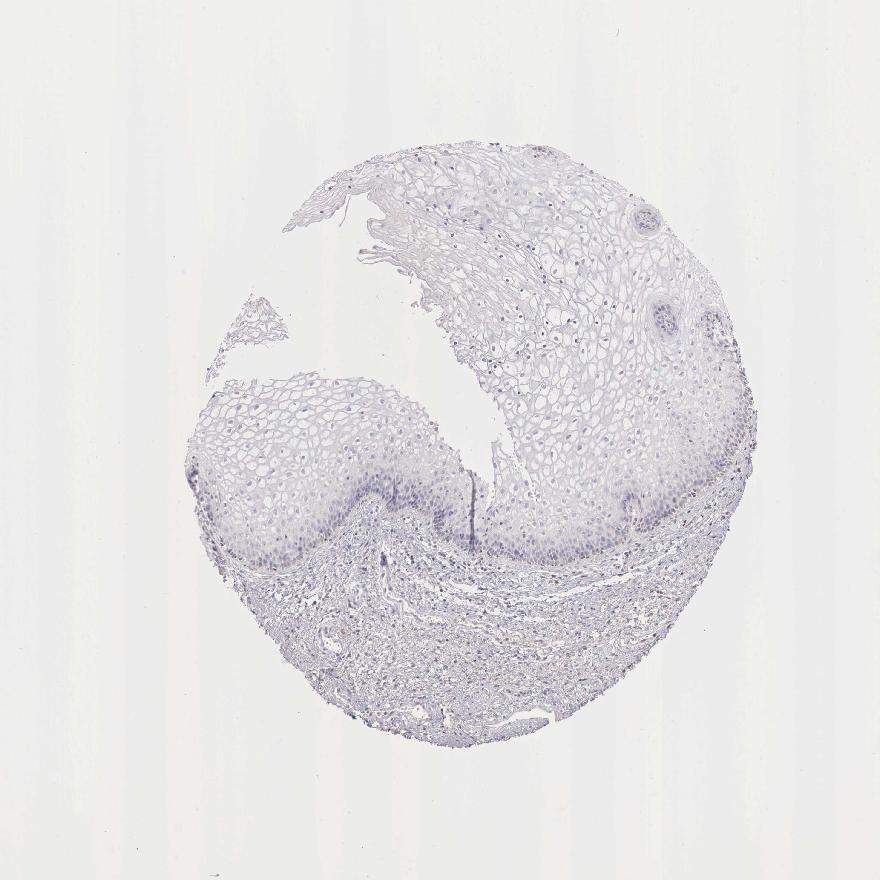

TISSUE PRIMARY DATA VAGINA Show tissue menu

Vagina

VAGINA - Antibody stainingi

Antibody staining in the annotated cell types in the current human tissue is reported as not detected, low, medium, or high, based on conventional immunohistochemistry profiling in selected tissues. This score is based on the combination of the staining intensity and fraction of stained cells.

Each image is clickable and will lead to virtual microscopy that enables deeper exploration of all samples and also displays staining intensity scores, fraction scores and subcellular localization as well as patient and tissue information for each sample.

Antibody HPA000339Antibody CAB025136Antibody CAB025269

Squamous epithelial cells Not detectedNot detectedNot detected